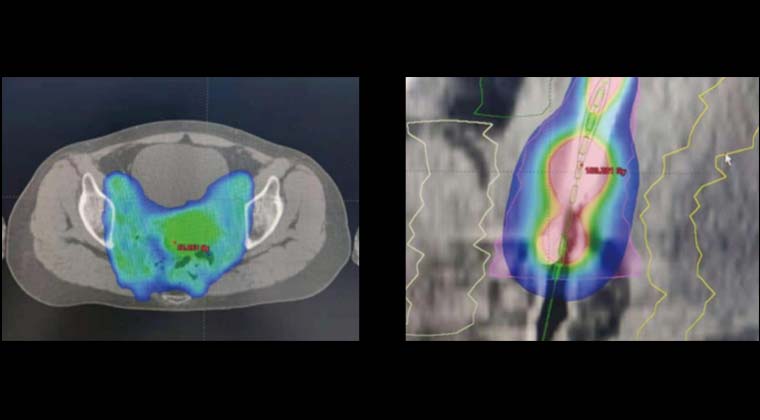

Рисунок 1: План лечения внешним облучением + брахитерапией с дистанционным введением источника

Рисунок 2 слева: До лечения

Рисунок 2 справа: После лечения